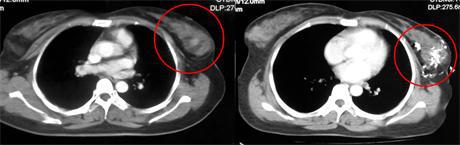

乳腺癌ct片图片,乳腺癌切除图片

我妈妈乳腺癌术后10个月做的胸部ct,能帮忙看一下情况

乳腺癌ct

肝癌ct图片